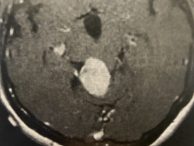

- Brain Tumors

- Brain Metastases

- Gliomas